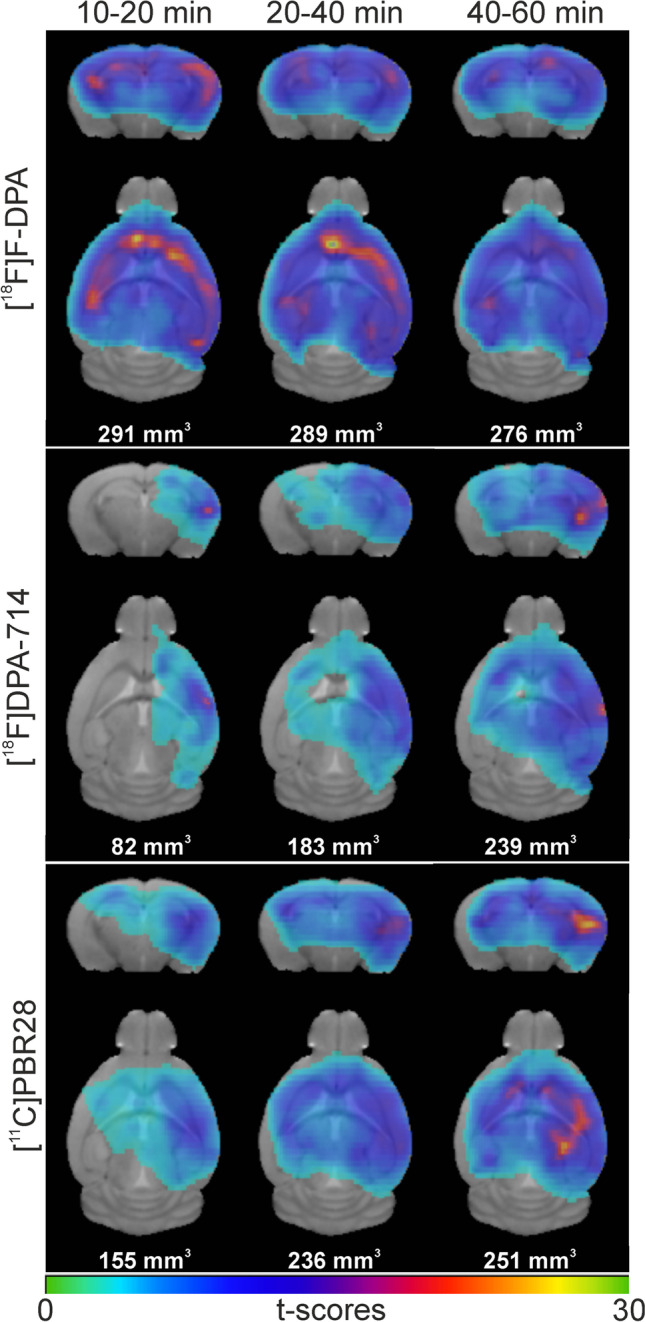

We performed a voxel-wise analysis of the PET images to study the differences in tracer uptake between WT and TG mice at 10–20, 20–40, and 40–60 min after injection at the voxel level. Figure 4 shows coronal and axial images of [18F]F-DPA, [18F]DPA-714, and [11C]PBR28 at the different time points and the cluster sizes. Due to the extensive signal, and after filtering, only a single cluster was detected. In the 10–20 min time frame, the cluster size for [18F]F-DPA was 292 mm3, while for [18F]DPA-714 and [11C]PBR28, the sizes were 83 mm3 and 156 mm3, respectively. In the next time frames, the [18F]DPA-714 and [11C]PBR28 cluster sizes increased significantly until the 40–60 min time frame. At this last time frame, the cluster sizes were 277 mm3 ([18F]F-DPA), 240 mm3 ([18F]DPA-714), and 251 mm3 ([11C]PBR28). Cortical and hippocampal uptake areas of higher significance are indicated by the higher t-scores. The voxel-based analysis also showed no differences in uptake between WT and TG in the CB.

Fig. 4.

Voxel-wise two-sample t-test images and cluster sizes comparison of [18F]F-DPA (top), [18F]DPA-714 (middle), and [11C]PBR28 (bottom) brain uptake at different periods after injection (10–20, 20–40, and 40–60 min)